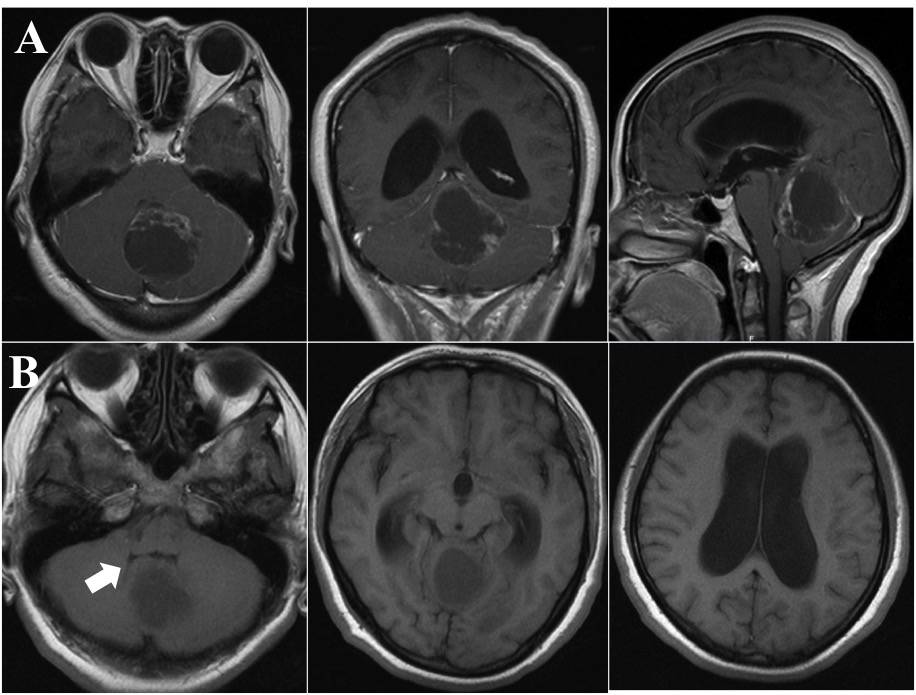

现患者术后4年余,门诊随访中,出院至今mRS评分0分。最近MRI增强复查,未见肿瘤复发(图3)。

图3. A. 术后5日头颅增强MRI;B. 术后4年余头颅增强MRI未见肿瘤复发。